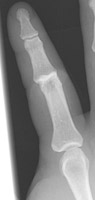

Named for injuries to baseball coaches, this term refers a dorsal dislocation of one of the proximal interphalangeal joints. Care must be made to determine if there is an associated volar plate fracture. With dorsal dislocations, the volar plate is usually detached from the middle phalanx. These injuries are due to hyperextension (such as from catching a ball). These injuries are usually managed nonoperatively, but if the collateral ligaments are disrupted, the joint will become unstable and arthroplasty will be required.

- Click on the image for a larger versionCLateral radiograph of the second digit. There is dorsal dislocation of the PIP joint. This case is unusual in that there is not an associated volar plate fracture because this is an open injury (notice the air).